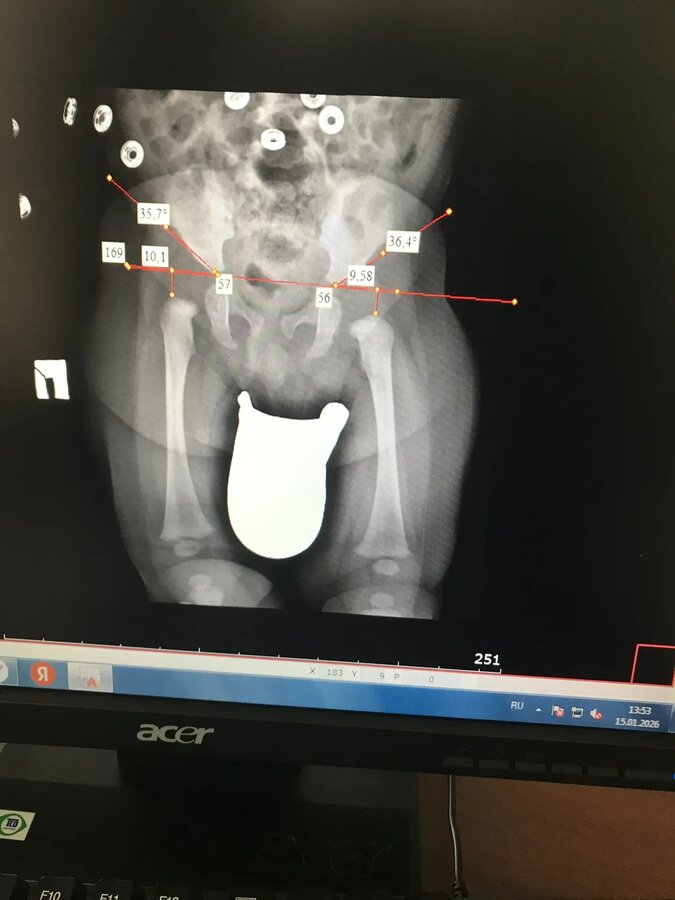

Дмитрий Олегович,здраствуйте, в 3,5 месяца после рентгена поставили диагноз дисплазия ТБС, прописали стремена Павлика,стоит ли ещё что то добавить к лечению?насколько все плохо,есть ли шанс ,что данный метод поможет,физио проходили ещё и 1,5 месяца,там делали УЗИ, были небольшие отклонения от нормы,ничего кроме массажа и физио не прописали,все рекомендации выполняли,сейчас 4 месяца нам

Дмитрий Олегович,здраствуйте, в 3,5 месяца после рентгена поставили диагноз дисплазия ТБС, прописали стремена Павлика,стоит ли ещё что то добавить к лечению?насколько все плохо,есть ли шанс ,что данный метод поможет,физио проходили ещё и 1,5 месяца,там делали УЗИ, были небольшие отклонения от нормы,ничего кроме массажа и физио не прописали,все рекомендации выполняли,сейчас 4 месяца нам 4 месяца